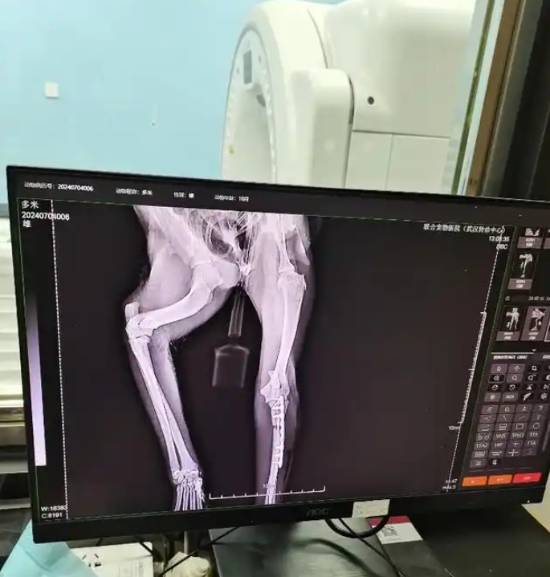

送医后经诊断,多米两条后腿都有伤,一条骨折一条韧带断裂,还伴随肺挫伤等多种症状,情况危急。但幸运的是,经两天抢救以及后续的骨折手术和长达半年的康复,在花掉近两万元医疗费后,多米恢复了健康。